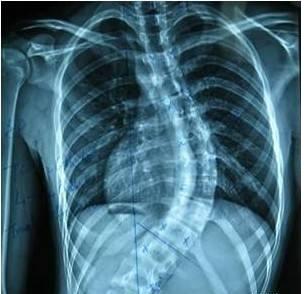

• 强直性脊柱炎患者治疗存在3个误区

• 强直性脊柱炎怎样预防效果好?

• 强直性脊柱炎的早期症状有哪些?

• 引起强直性脊柱炎出现的发病原因都有哪些?

• 强直性脊柱炎的这四大危害患者决不可轻视!

• 得了强直性脊柱炎能治好吗?

• 生活中怎么预防强直性脊柱炎比较好?

• 日常强直患者的保健方法有哪些?

• 老年人的强直性脊柱炎预防策略

• 生活中诱发强直性脊柱炎病因有哪些?